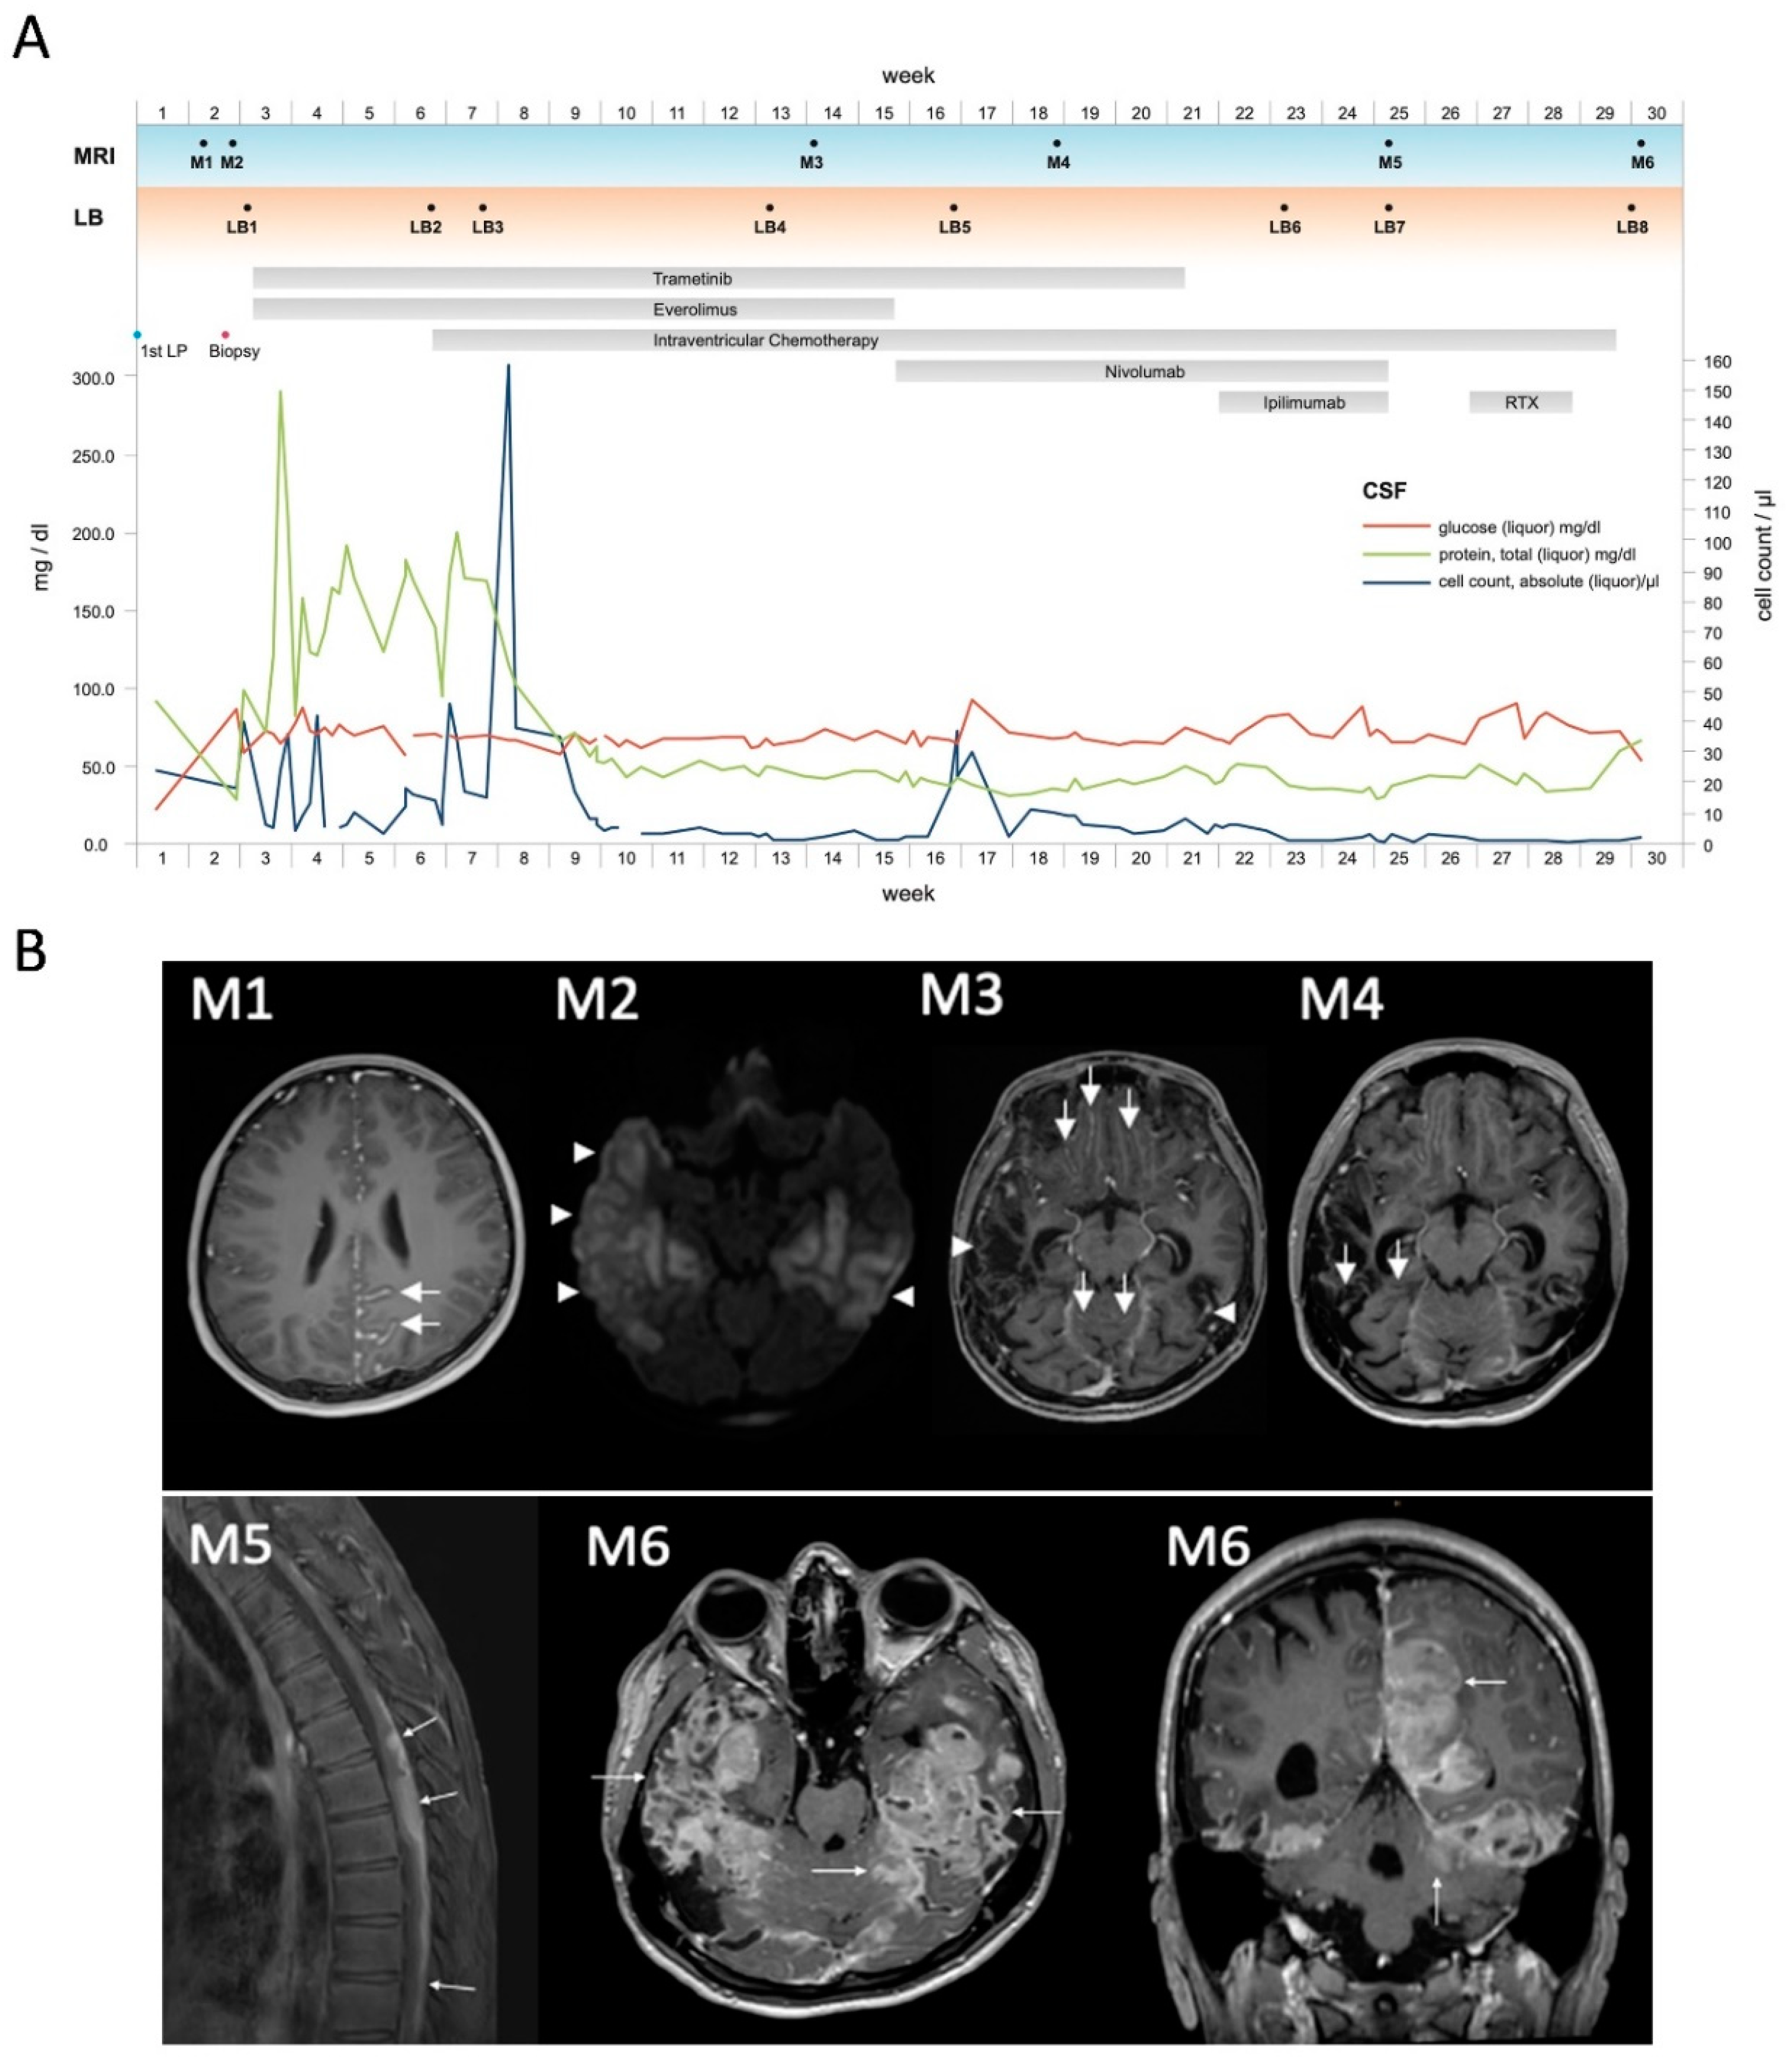

3.1. Illustrative Case